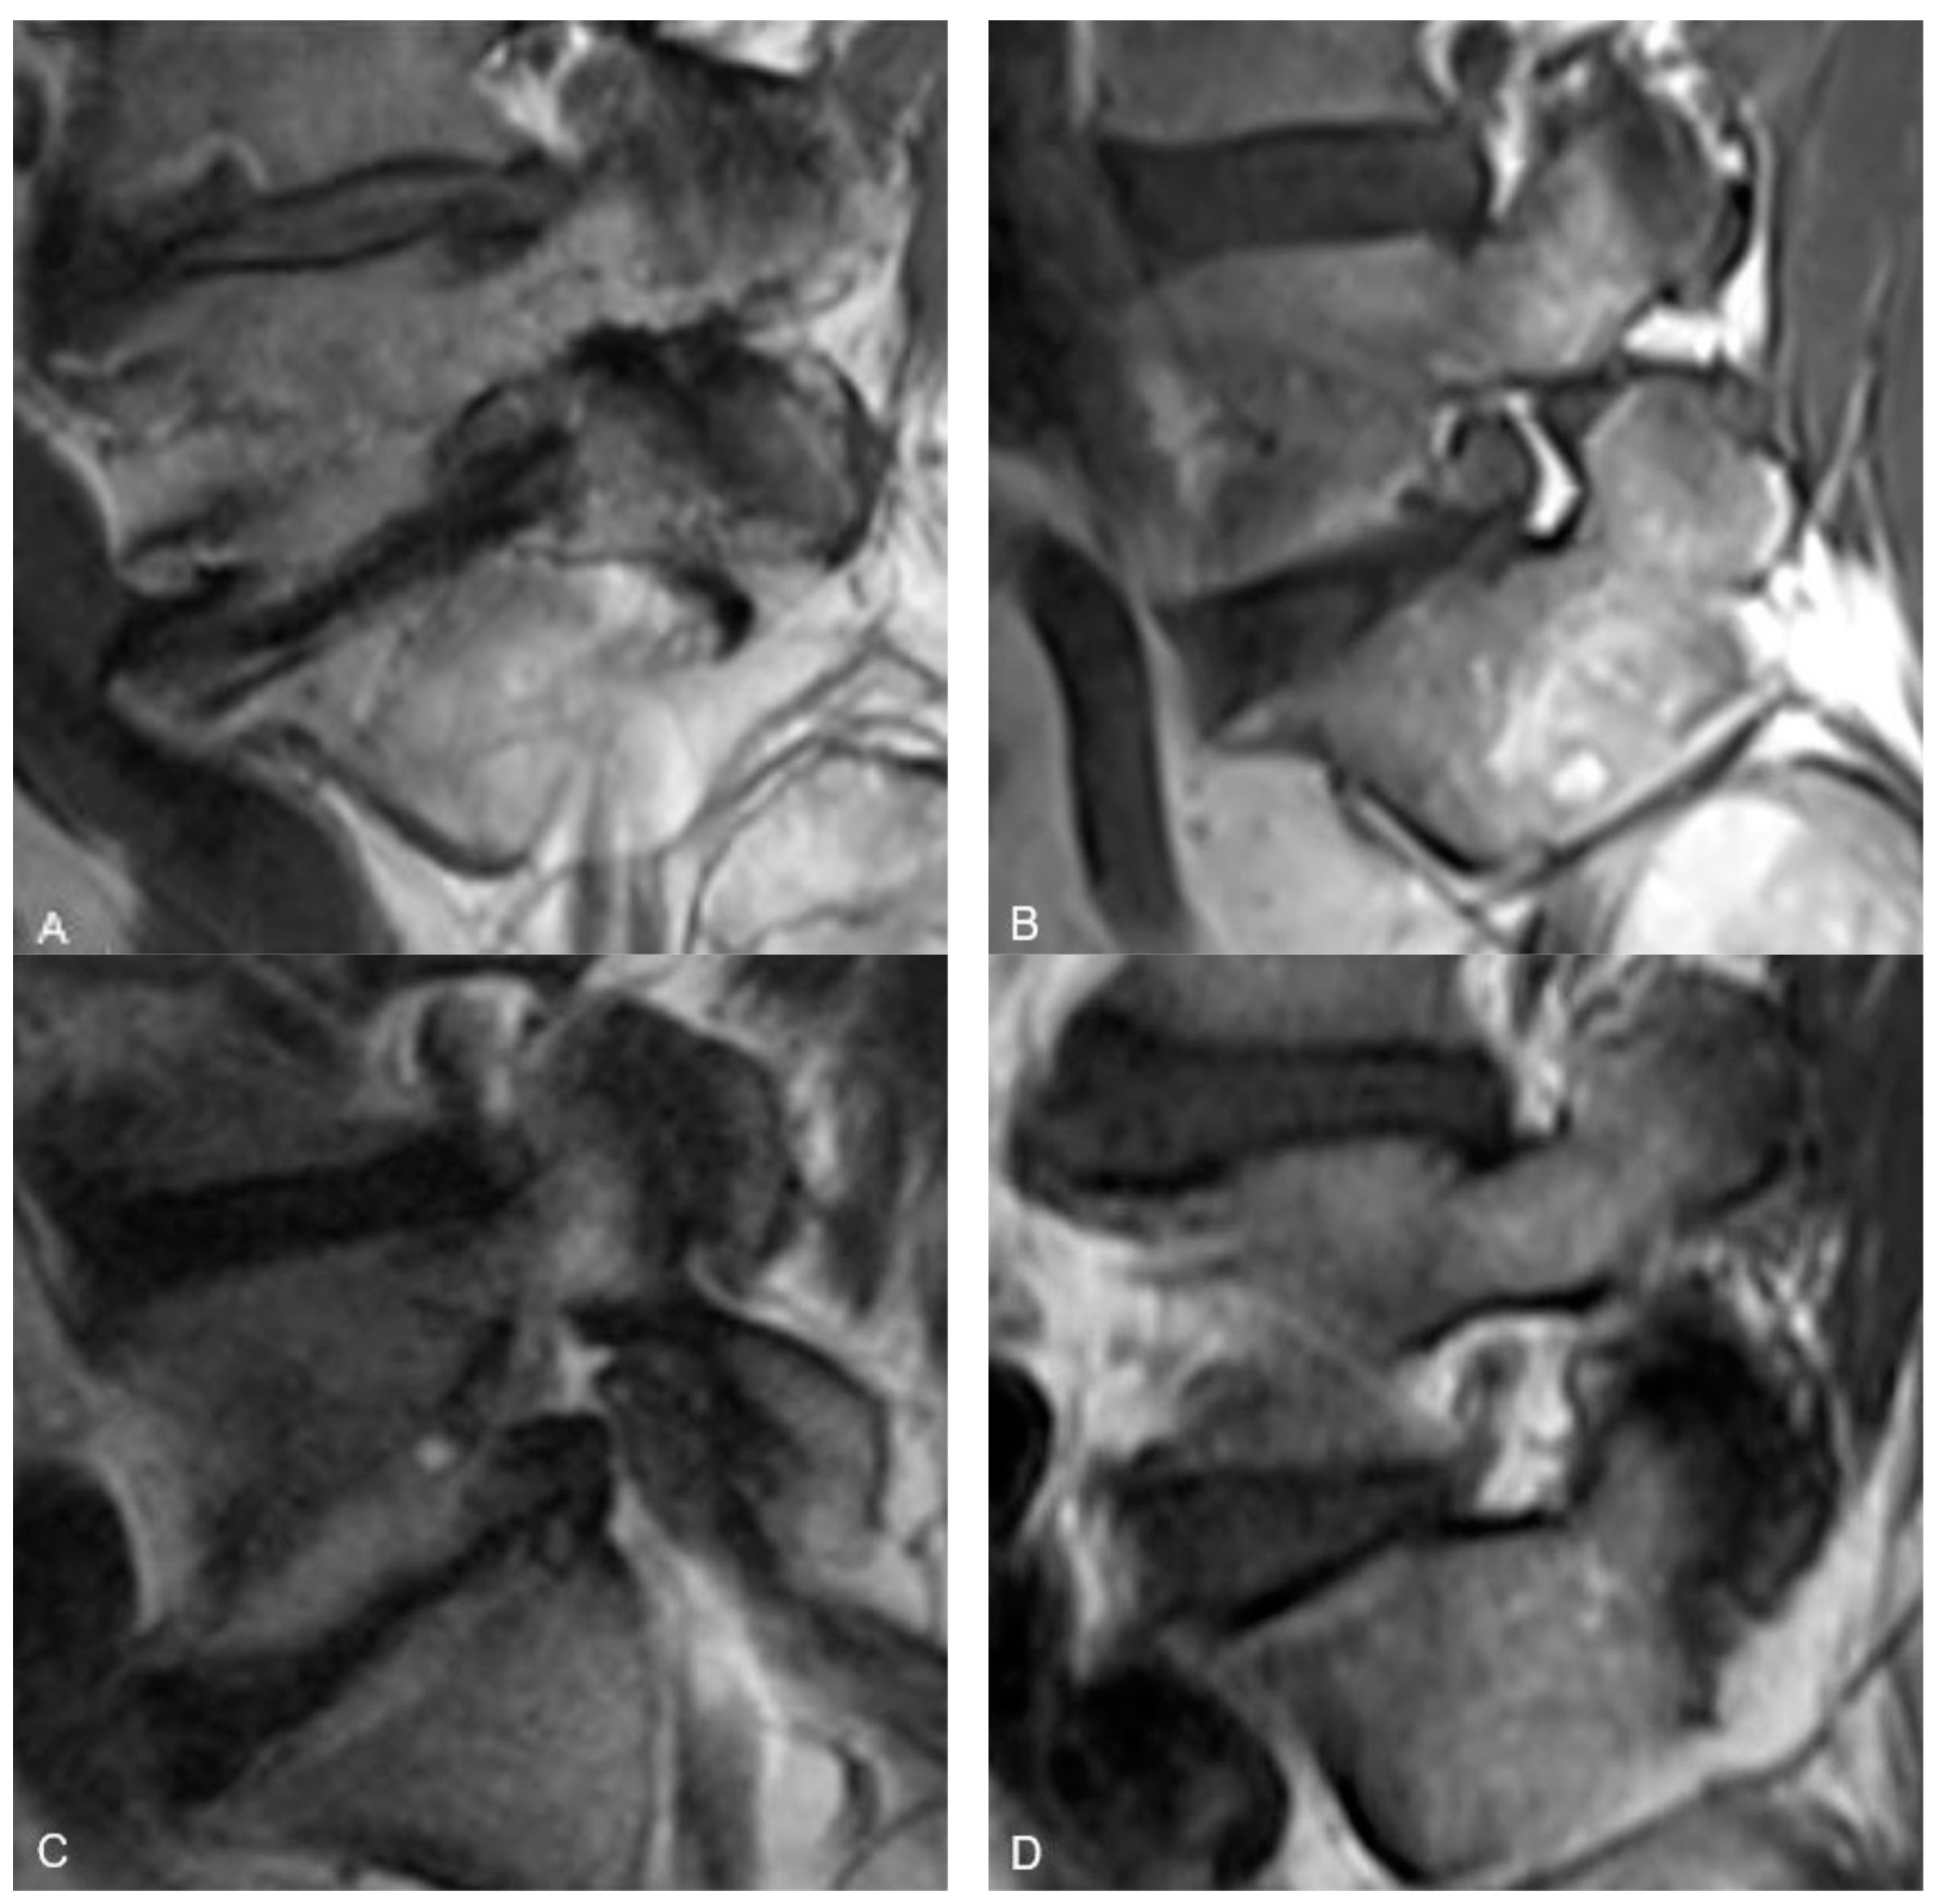

The semi-quantitative method for determining the amount of fat in both the antero-superior and the postero-inferior aspects of the neural foramina was based on the diameter of a 22-gauge needle, which is ~0.7 mm. With this as the standard, the reviewers were instructed to grade the fat as “None” if there was less than 0.8 mm of distance in any direction between nerve and bone/disc material, “Minimal” if there was 0.8 mm to 2.5 mm of distance, and “Substantial” if there was more than 2.5 mm of distance. These numbers reflect, in essence, a space too small to accommodate a 22-gauge needle, a space that is 1–3 times the size of a 22-gauge needle, or a space that can accommodate more than 3 times the diameter of a 22-gauge needle (Figure 1).

Figure 1.

Representative sagittal T1w MR images at the level of the L5-S1 neural foramen demonstrating the foraminal fat grading system. (A) demonstrates “No fat” in either the antero-superior or postero-inferior portions of the foramen. (B) demonstrates “Minimal fat” in the antero-superior foramen and “Substantial fat” in the postero-inferior foramen. (C) demonstrates “No fat” in the antero-superior foramen and “Minimal fat” in the postero-inferior foramen. (D) demonstrates “Substantial fat” in both the antero-superior and postero-inferior foramen.